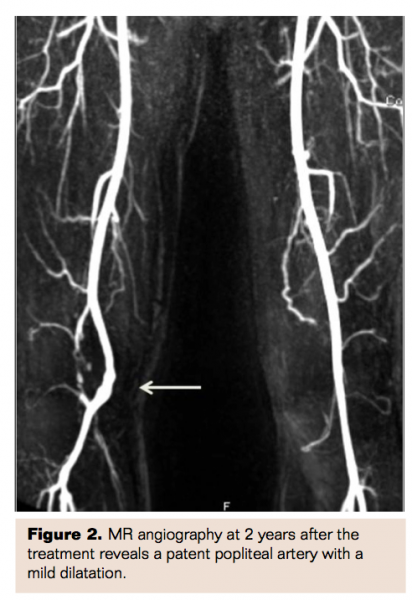

The surgical and endovascular outcomes were good and there were no intraoperative or postoperative complications. The patients had a median follow-up of 64 months (range, 41-100 months). Three of 5 patients had an uneventful, long-term follow-up and did not need any further intervention. Follow-up CDUS or MRA revealed patent popliteal arteries in these patients, but 1 patient had a small popliteal artery aneurysm visualized by MRA at 2 years (Figure 2). Two patients had recurrent thrombosis of the popliteal artery after treatment. One of these patients had repeated endovascular treatments at 4 and 18 months because of rethrombosis of the femoral and popliteal arteries. This oldest patient had the worst distal run-off (distal embolic occlusions of all